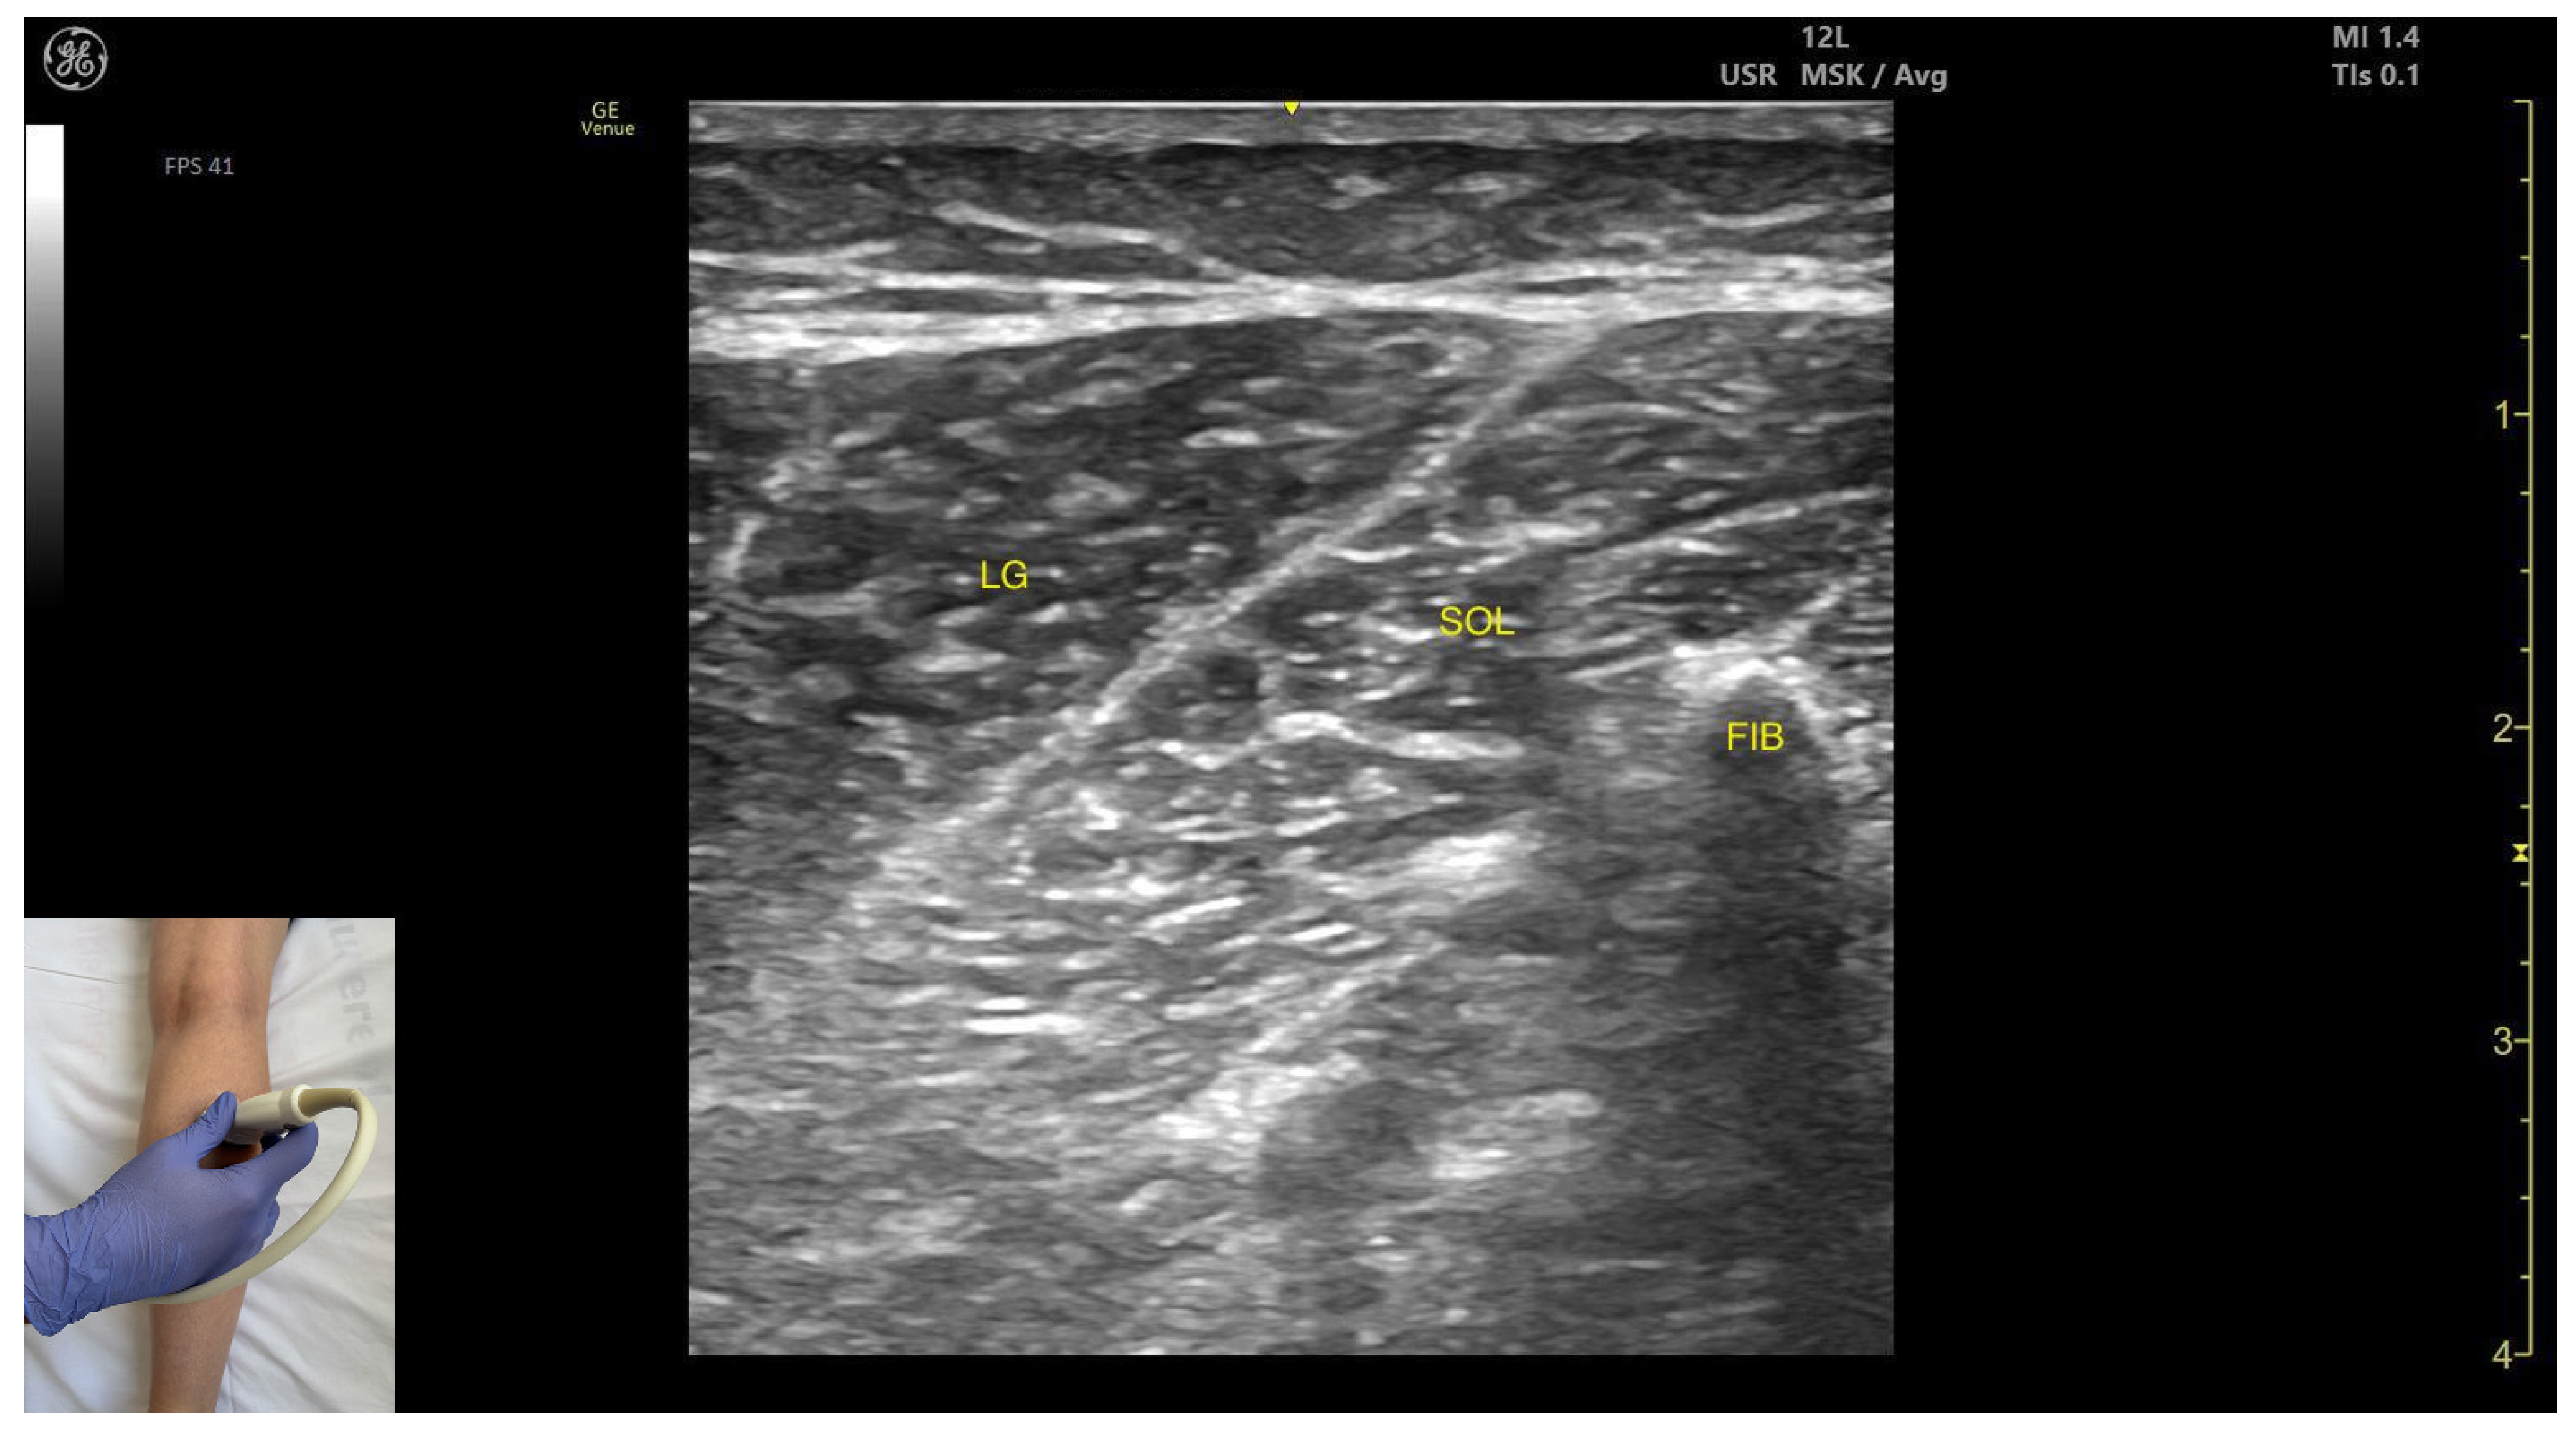

- Muscle position: It is the most superficial and prominent muscle in the posterior compartment of the leg, and one of the largest in the region. The soleus—and, if present, the plantaris—is located deep to it.

- External fascia: It presents a well-defined fascia separating it from the subcutaneous plane, soleus, and plantaris muscle/tendon, during BoNT-A injection.

- Dynamic evaluation: During dynamic evaluation, scanning toward the ankle joint, the lateral head of the gastrocnemius progressively decreases and eventually disappears while the soleus increases in thickness; distally, both merge into the Achilles tendon with the soleus (and plantaris, if present). On medial scanning the intersection of the lateral and medial gastrocnemius heads is visualized—the medial sural cutaneous nerve typically courses between these heads. Because the gastrocnemius is a biarticular muscle crossing both the knee and ankle joints, it is assessed with the knee extended to place the muscle on maximal stretch and thereby reveal its contribution to ankle plantarflexion. Muscle contraction is visible during plantar flexion of the foot at the ankle joint, as well as during knee flexion.

- Muscle morphology: It appears as a flat muscle in the posterior compartment of the leg.

- Muscle position: At this level, the soleus lies deep to the intersection of the gastrocnemius heads, within which the medial sural cutaneous nerve courses.

- External fascia: A pronounced fascia separates it from the subcutaneous plane, gastrocnemius muscles, and the plantaris muscle/tendon (if present), which is relevant during BoNT-A injection.

- Dynamic evaluation: During dynamic evaluation, scanning laterally reveals enlargement of the lateral gastrocnemius head, and deep to the soleus, the neurovascular bundle emerges, comprising the posterior tibial artery, the two posterior tibial veins, and the posterior tibial nerve. Medial scanning highlights enlargement of the medial head of the gastrocnemius (MG), while the neurovascular bundle maintains its anatomical course. The soleus, a monoarticular muscle acting exclusively at the ankle joint, is optimally assessed with the knee flexed; this positioning diminishes gastrocnemius involvement, allowing for isolated evaluation of soleus contractile activity via EMG or dynamic ultrasound imaging. Muscle contraction is visible during plantar flexion maneuvers of the foot at the ankle joint.

| Lateral Head of Gastrocnemius | ~8 cm distal to the popliteal crease, on the lateral side | Medial sural cutaneous nerve (superficial), soleus and plantaris muscle/tendon if present (deep) | Transverse scan on the posterior aspect of the leg | Avoid medial sural cutaneous nerve injury |

| Soleus | ~8 cm distal to the popliteal crease on the midline | Gastrocnemius (superficial) and plantaris muscle/tendon (if present); posterior tibial artery, tibial veins, and the posterior tibial nerve (deep) | Transverse scan on the posterior aspect of the leg | Avoid neurovascular injury |